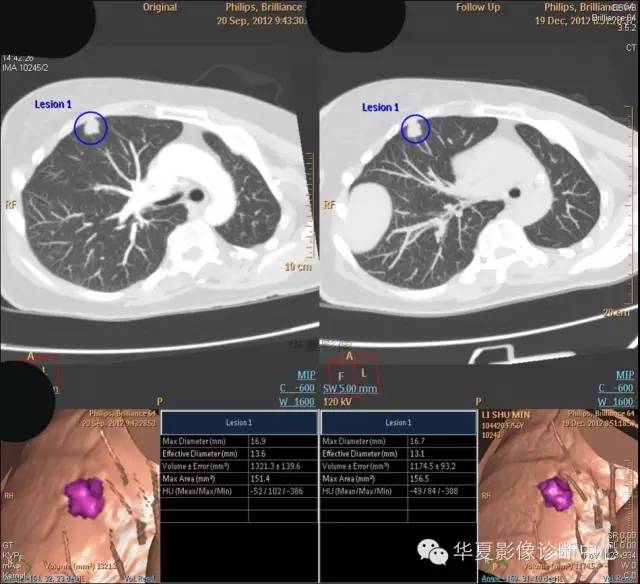

女,56岁,其父因肺癌去世,自觉胸部疼痛不适来诊要求拍胸片。

检查所见:

1.右肺上叶:肺组织1块,大小13×4×7cm。切面棕红色。2.右肺上叶肿物:灰白色组织一块,大小3×1×1.5cm。切面灰白色。3.右肺中叶结节:灰白色绿豆大组织1块。4.淋巴结:灰黑色绿豆大组织1块。

检查结论:

(右)肺中分化鳞状细胞癌。浸及胸膜。支气管残端切净。淋巴结未见癌转移(0/10)。